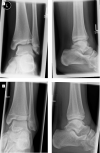

Aims: Understanding the orientation of fracture lines and mechanisms is the essential key to sufficient surgical therapy, but there is still a lack of visualization and teaching methods in traumatology and fracture theory. 3D-printed models offer easy approach to those fractures. This paper explains the use of the teaching possibility with 3-dimensional models of transitional fractures of the ankle.

Methods and results: For generating 3D printable models, already obtained CT data were used and segmented into its different tissues, especially parts concerning the fracture. After the segmentation process, the models were produced with FFF (fused filament fabrication) printing technology. The fracture models then were used for hands-on teaching courses in AO course (Arbeitsgemeinschaft für Osteosynthesefragen) of pediatric traumatology in 2020 in Frankfurt. In the course fracture anatomy with typical fracture lines, approaches, and screw placement could be shown, discussed and practiced.

Conclusion: The study shows the use of 3D-printed teaching models and helps to understand complicated fractures, in this case, transitional fractures of the ankle. The teaching method can be adapted to numerous other use cases.